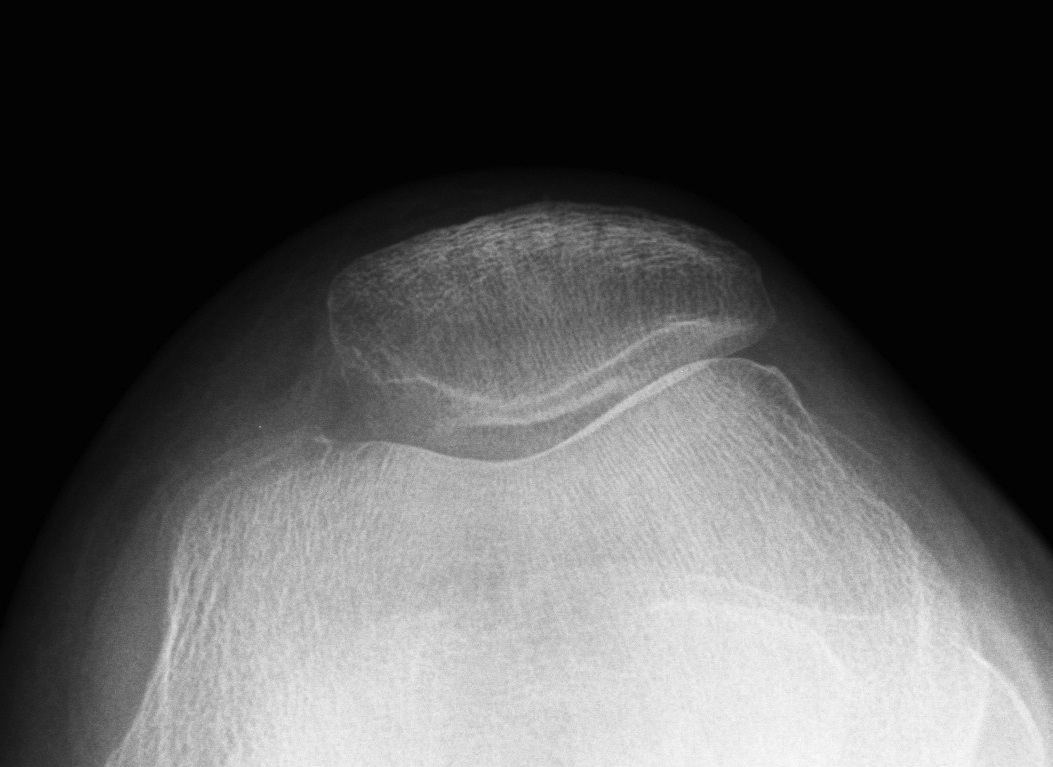

2. Assess Trochlea Dysplasia

Dejour Crossover Sign

- lateral x-ray at 30o with condyles superimposed

- identify base of trochlea

Abnormal / Crossover

- line of floor of trochlea crosses lateral lip of condyle

- indicates trochlea is deficient proximally

Trochlea depth

- < 8 mm shallow

Dejour grading system 1 - IV